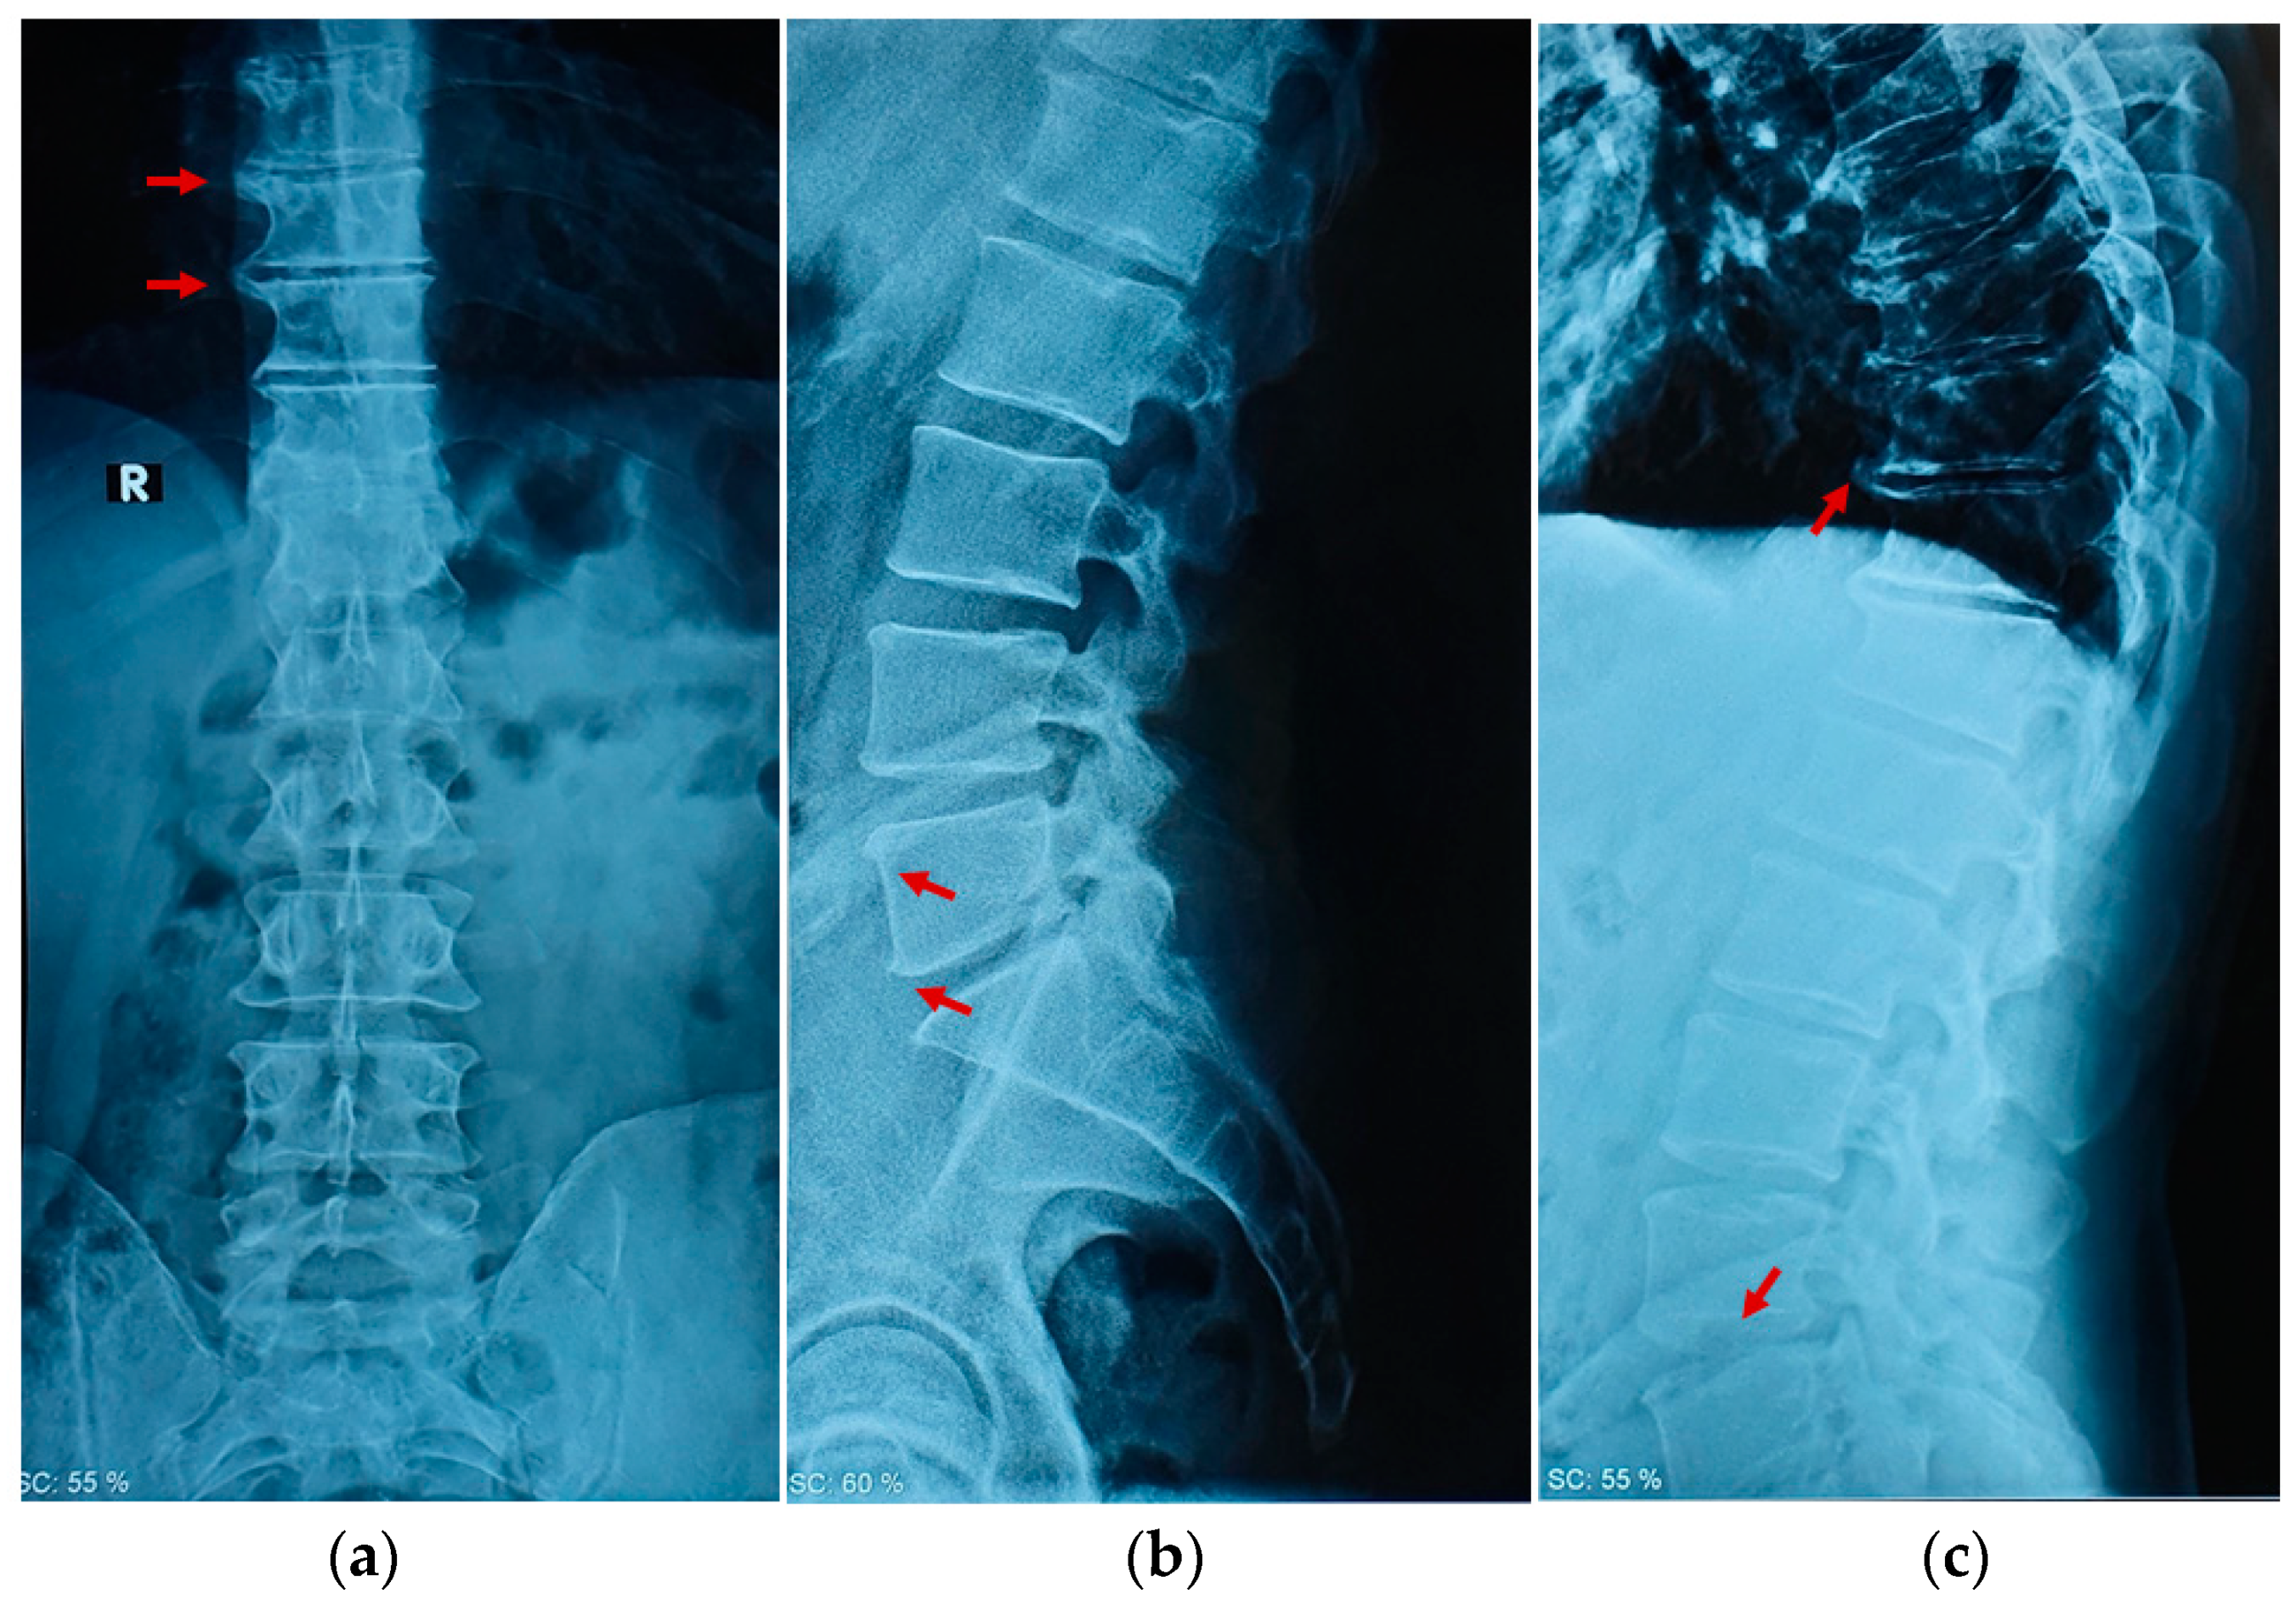

2. Case Report

2.1. Clinical Examination